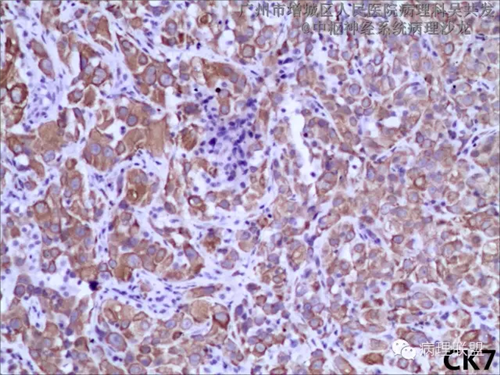

免疫组化HE切片图